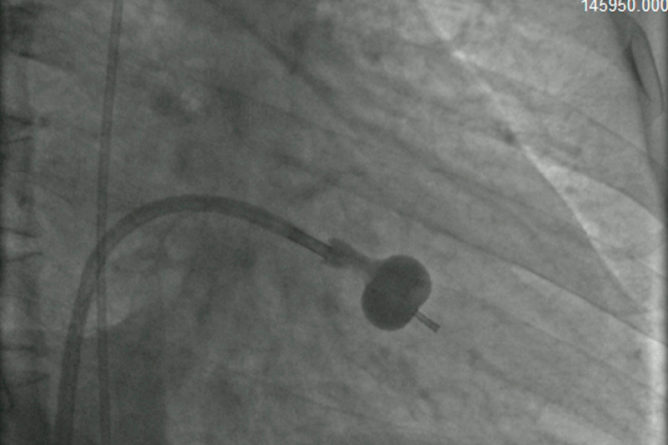

Device Closure

Birth defects in the heart are of many types. ASD is Atrial Septal Defect. It is a defect…